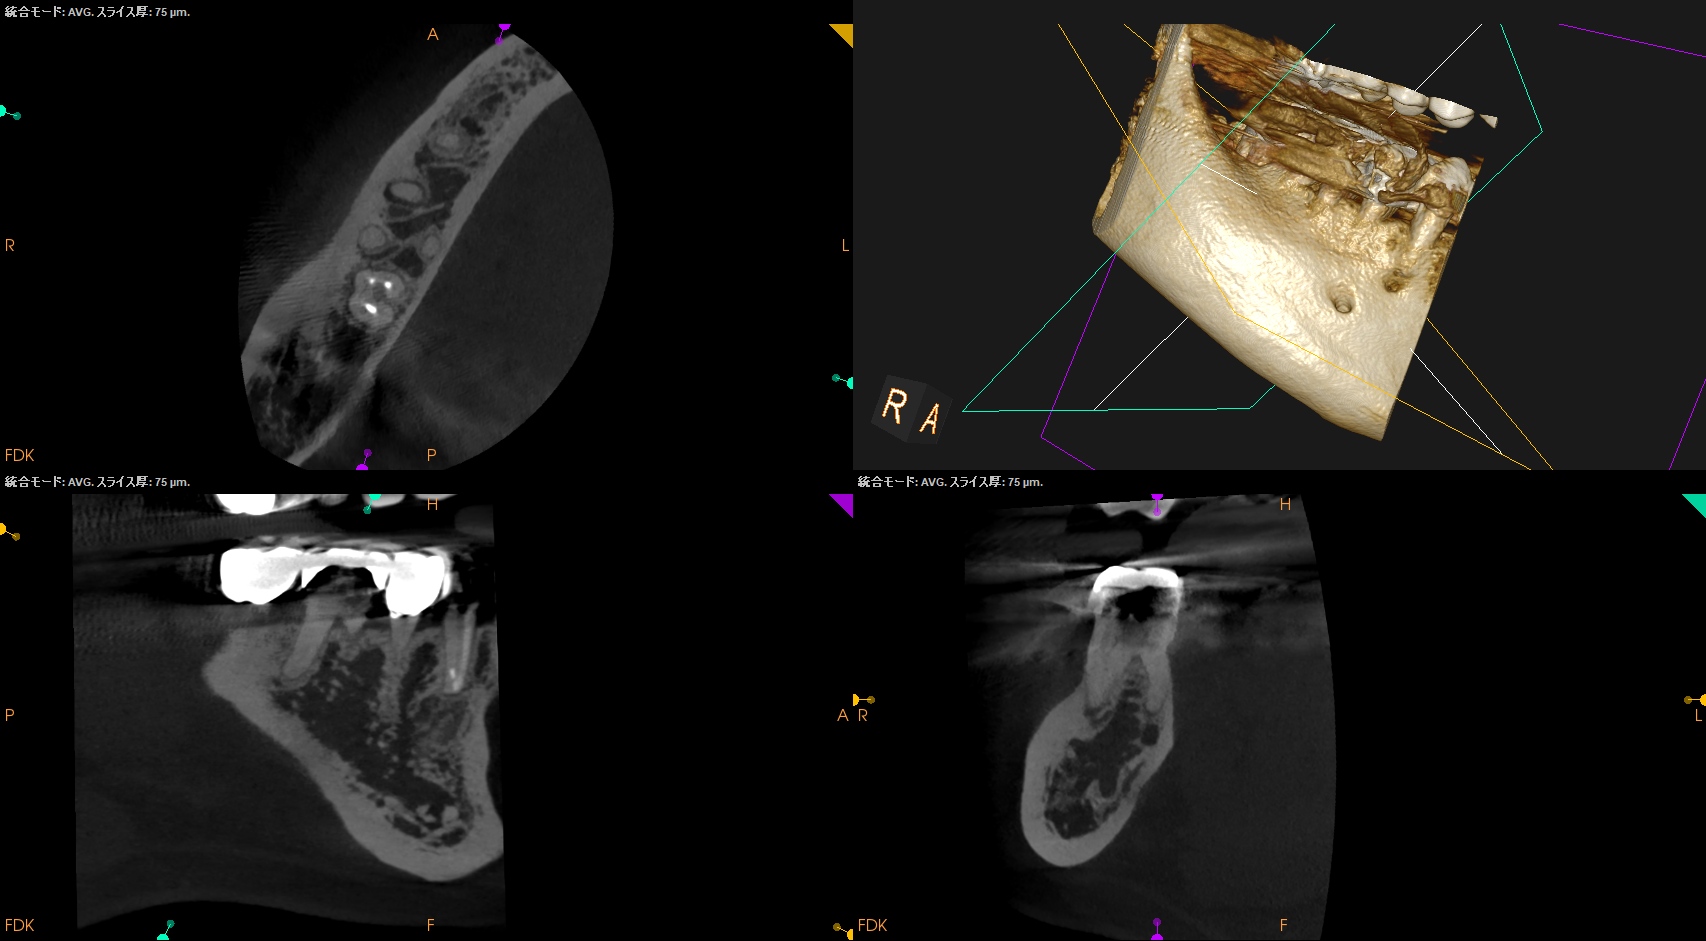

術後にPA, CBCTを撮影した。

MB

ML

D

Radix

ということで問題ないだろう。